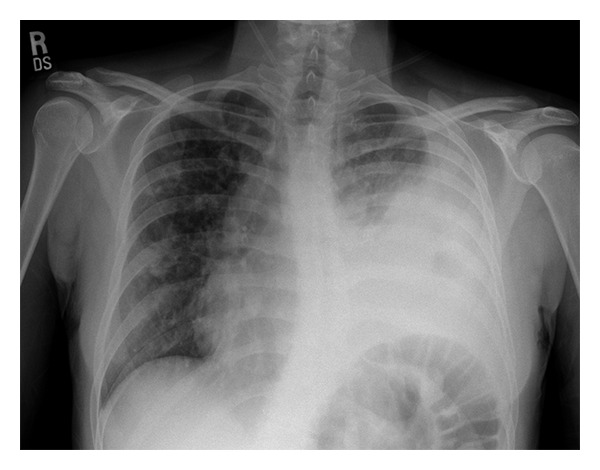

• Input 3: What is seen in the X-ray and what should be done?

Image:

• Visual Med-Alpaca: Bilateral infiltrates and bilateral pleural effusion seen in a chest x-ray may indicate a respiratory infection or other respiratory conditions such as pneumonia pulmonary edema, or pleural effusion, it is important to consult a medical professional for a proper diagnosis and treatment plan.

• VQA Medical Model: the decubitus

• Automatic Radiology Report Generation (Image-only): near complete opacification of the left hemi thorax with only a small amount of residual aerated lung in the left upper lobe .

• ChatGPT (GPT-3.5-Turbo) + Automatic Radiology Report Generation (Image-only): Opacification of the lung on an X-ray indicates that there is an abnormality in the lung tissue. In this case, the near-complete opacification of the left hemithorax with only a small amount of residual aerated lung in the left upper lobe suggests that there is likely a significant pathology present in the left lung. Possible causes of this finding include pneumonia, lung abscess, tumor or mass, or pleural effusion (fluid accumulation around the lung). It is important to determine the underlying cause of this finding as soon as possible. A follow-up diagnostic workup may include a CT scan of the chest, sputum culture, bronchoscopy, and/or a biopsy of any suspicious areas in the lung. The appropriate treatment will depend on the underlying cause, but it may include antibiotics, drainage of any fluid collections, or surgery to remove any masses or tumors. Prompt evaluation and treatment are necessary to prevent complications and improve outcomes.